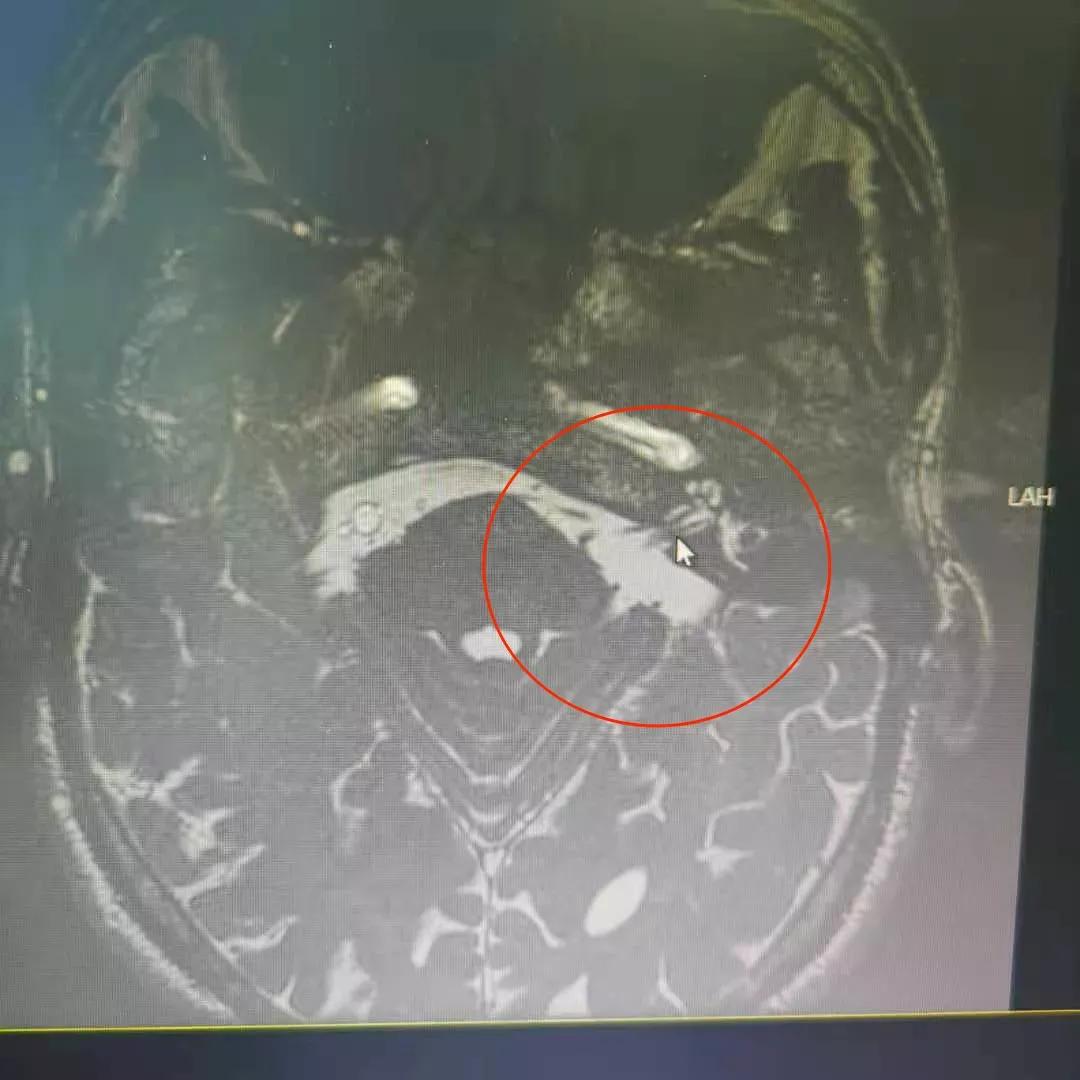

术前头颅MR上所示,三叉神经根部被小血管压迫